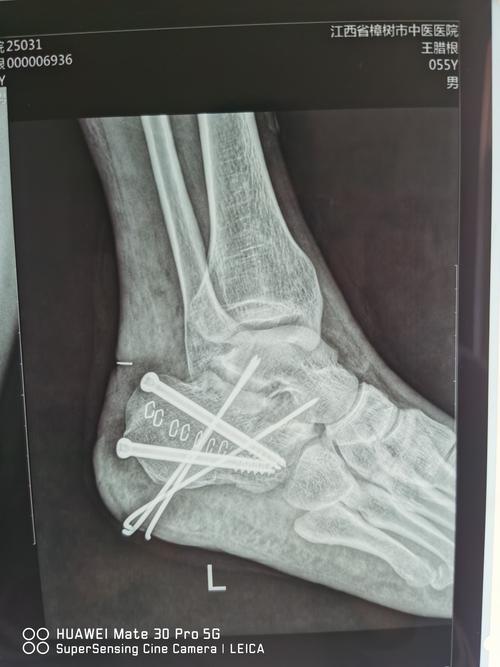

跗骨窦小切口入路治疗跟骨粉碎性骨折 病案一例

跟痛症,跟骨刺,足底跖筋膜炎(跟骨x线片)

足x线的正常表现及常见病变